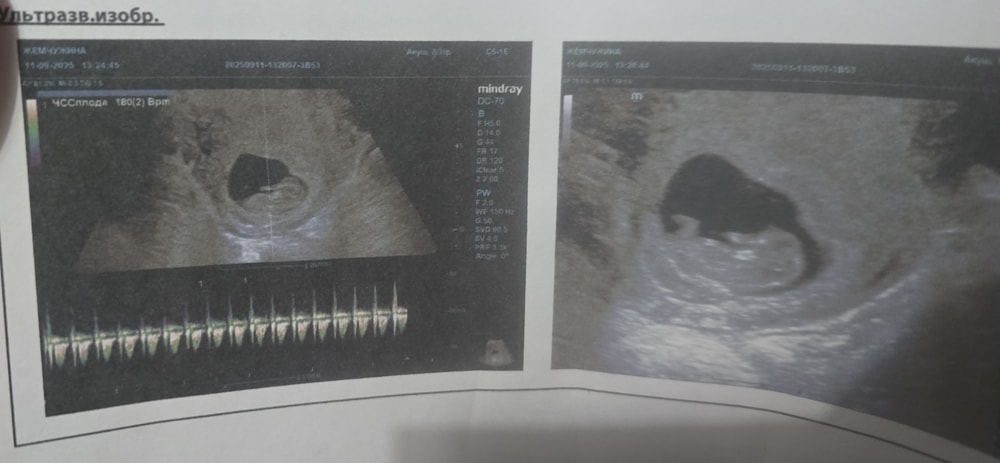

Угроза или нет, не могу понять. Беременность 10 недель.

Выделения, воды, отхождение пробкиУтром увидела розоватые выделения со слизью, сходила на УЗИ. Узистка сказала, что всё хорошо, сердцебиение есть, и она ничего страшного не видит. К гинекологу смогу сходить завтра. Пожалуйста, подскажите, что это может быть, дискомфорта и боли нет. Как-то стрёмно выкладывать фото выделение.